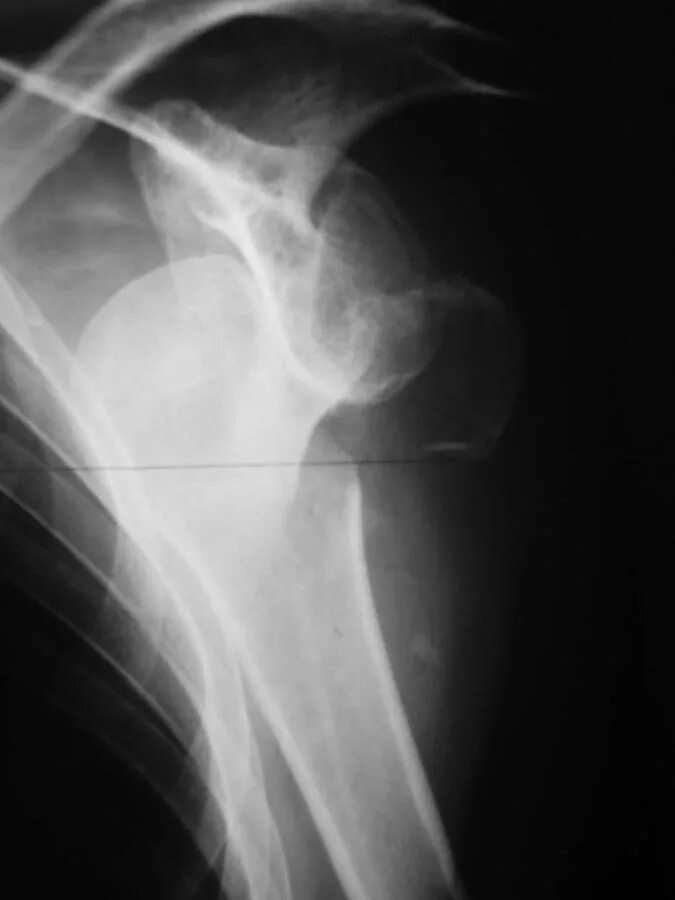

Вывих плеча у пожилых